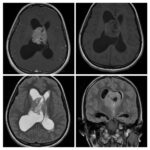

Neurosurgery and neuroradiology always go hand in hand. This little weekly activity is going to enhance the scan reading skills of our audience in an interactive way. Waiting for the answer for a week will keep the curiosity alive and will keep our target audience hooked to the website. It will prove to be a seamless share of knowledge and reading skills.

Dr. Saqib Kamran Bakhshi started the PANS Weekly Image Challenge in 2022, and his creativity and efforts made it a popular activity; engaging trainees and consultants in Pakistan and abroad.